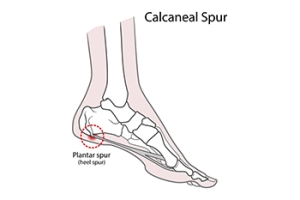

It is a common misconception that heel spurs are the primary cause of heel pain. In reality, heel spurs, which are bony projections on the heel bone, are often found by having an X-ray taken, and cause pain in only 5 percent of individuals with them. The majority of heel pain is generally due to plantar fasciitis, an inflammation of the plantar fascia tissue which stretches from the heel to the toes. While many individuals with plantar fasciitis also have heel spurs, the pain is typically from the damaged plantar fascia, not the spurs themselves. Heel spur syndrome and plantar fasciitis share similar risk factors, like athletic stress, obesity, calf tightness, high arches, and possibly osteoarthritis. Both conditions often respond to non-surgical treatments, including rest, footwear changes, and stretching. If these do not work, injections or plantar fasciotomy surgery might be recommended, though the heel spur is typically not removed during surgery. If you have heel pain, it is strongly suggested that you make an appointment with a podiatrist for a proper diagnosis and correct treatment methods.

Heel spurs are formed by calcium deposits on the back of the foot where the heel is. This can also be caused by small fragments of bone breaking off one section of the foot, attaching onto the back of the foot. Heel spurs can also be bone growth on the back of the foot and may grow in the direction of the arch of the foot.

Older individuals usually suffer from heel spurs and pain sometimes intensifies with age. One of the main condition's spurs are related to is plantar fasciitis.

Heel spurs are calcium deposits that cause bone protrusions on the heel bone. Heel spurs are usually associated with plantar fasciitis, which occurs when the plantar fasciitis in the foot becomes inflamed. Typically, heel spurs don’t cause any symptoms. However, they can produce chronic or intermittent heel pain. Those who have had the condition often describe the irritation as a stabbing pain.